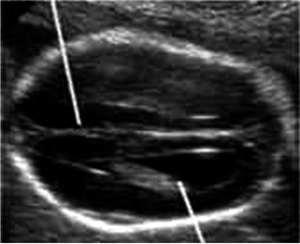

Εικόνα 2. Διαθαλαμική απεικόνιση κρανίου. Μέτρηση BPD (γραμμή), δρέπανο (μακρύ βέλος), οπτικοί θάλαμοι (λεπτό βέλος) και διαφανές διάφραγμα (κοντό βέλος). Εικόνα 3. Διαπαρεγκεφαλιδική απεικόνιση. Εμφανής η παρεγκεφαλίδα, η μεγάλη δεξαμενή (μακρύ βέλος), οι οπτικοί θάλαμοι (παχύ βέλος) και η αυχενική πτυχή (κοντό βέλος). Εικόνα 4. Διακοιλιακή απεικόνιση με μέτρηση της διαμέτρου της πλάγιας κοιλίας. Παρουσία χοριοειδούς πλέγματος εντός (βέλος).

Γ. Διακοιλιακή απεικόνιση

1. Μέτρηση διαμέτρου πλαγίων κοιλιών (φ.τ. <10mm): Διάταση βρίσκεται σε υδροκεφαλία, σε γενετικά σύνδρομα και σε τρισωμία 21.(10,15,23)

2. Απεικόνιση χοριοειδούς πλέγματος εντός των πλαγίων κοιλιών. Αναδύεται από το έσω τοίχωμα της κοιλίας.